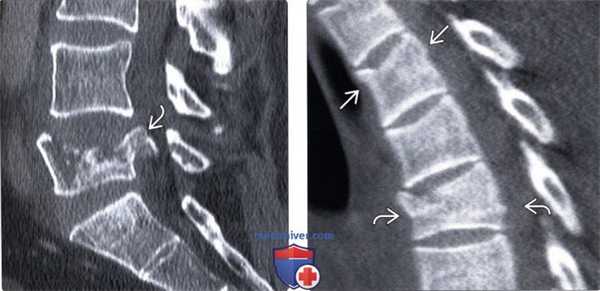

(Слева) КТ, сагиттальный срез: тяжелый взрывной перелом тела L5 позвонка со смещением крупного фрагментав спинномозговой канал. Несмотря на выраженный стеноз спинномозгового канала неврологического дефицита у данного пациента не было.

(Справа) КТ, сагиттальный срез: взрывные переломы Т5 и Т3 позвонков. Поскольку грудная клетка стабилизирована ребрами и грудиной, наличие здесь взрывных переломов свидетельствует о значительной силе травмирующего воздействия.